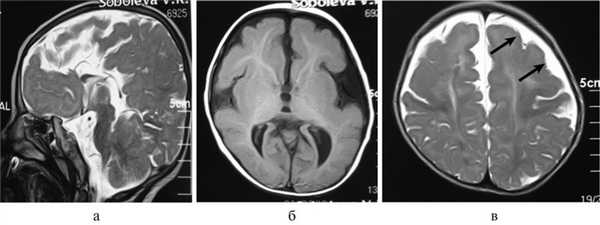

Рис. 2. Результаты обследования больной С., 8 лет. а, б, в — МРТ головного мозга (сагиттальная и аксиальная проекции): сочетание АМТ и диффузной пахигирии (стрелки).